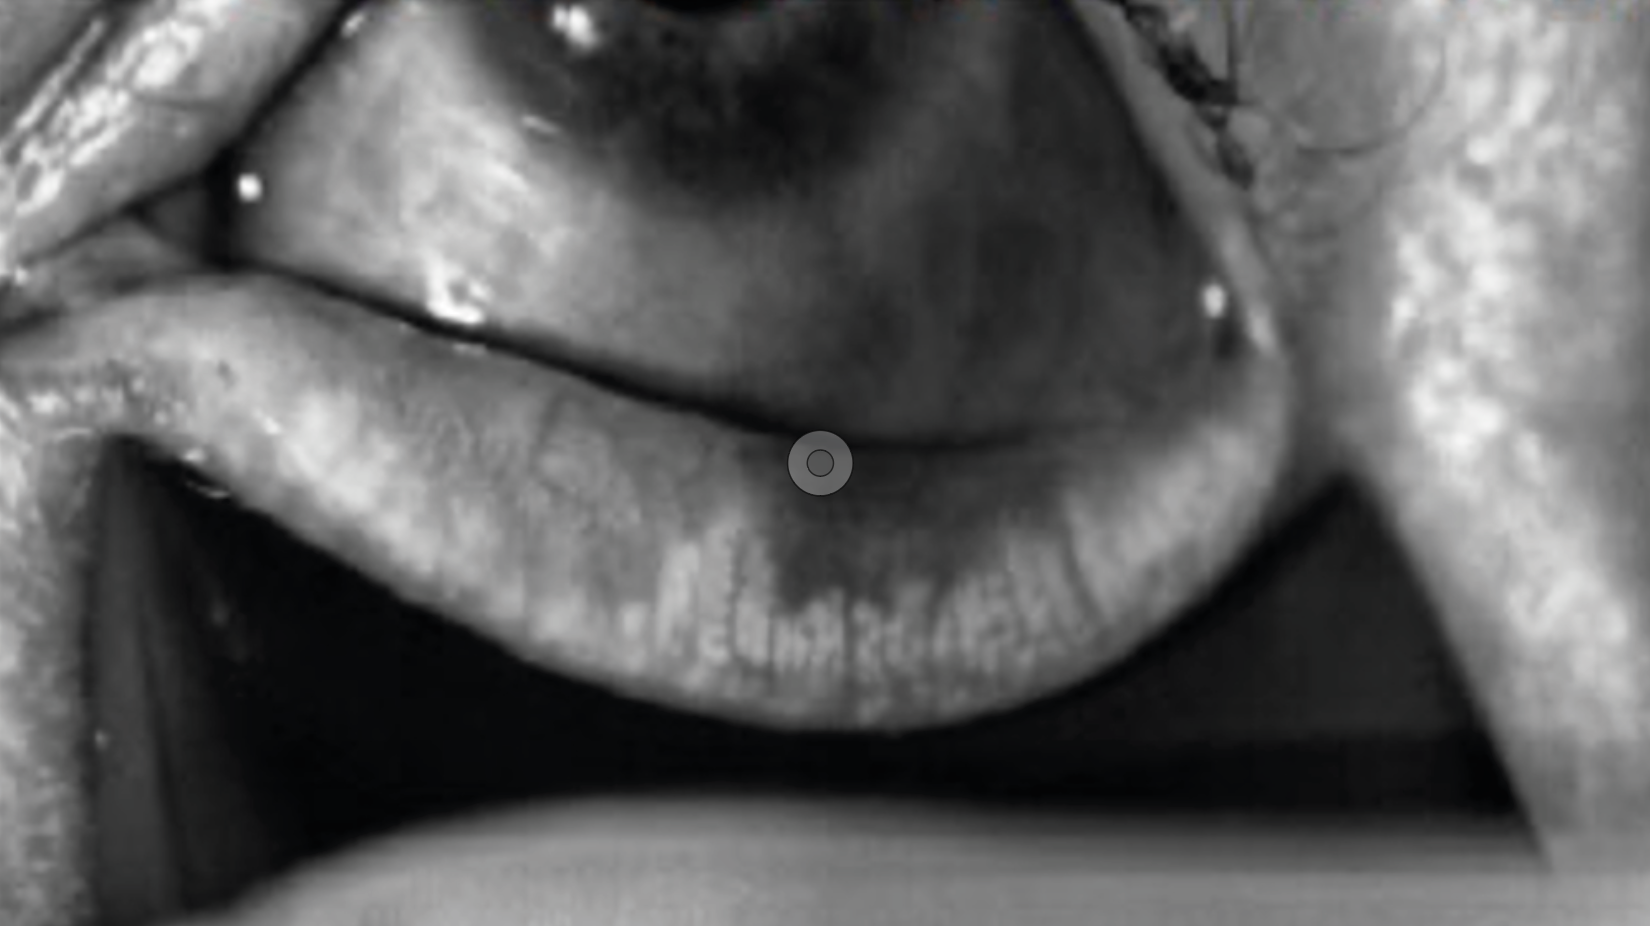

Neuropathie optique : quand la solution émerge de la conjonctive. À propos d’un cas clinique commenté

Figure 3. A. Taches de Bitôt OD/OG au moment du diagnostic en lumière blanche, puis en lumière bleue avec instillation de fluorescéine : notez l’aspect « vers luisants » de la conjonctive temporale.

B. Disparition des taches à 3 mois de la supplémentation vitaminique OD/OG.